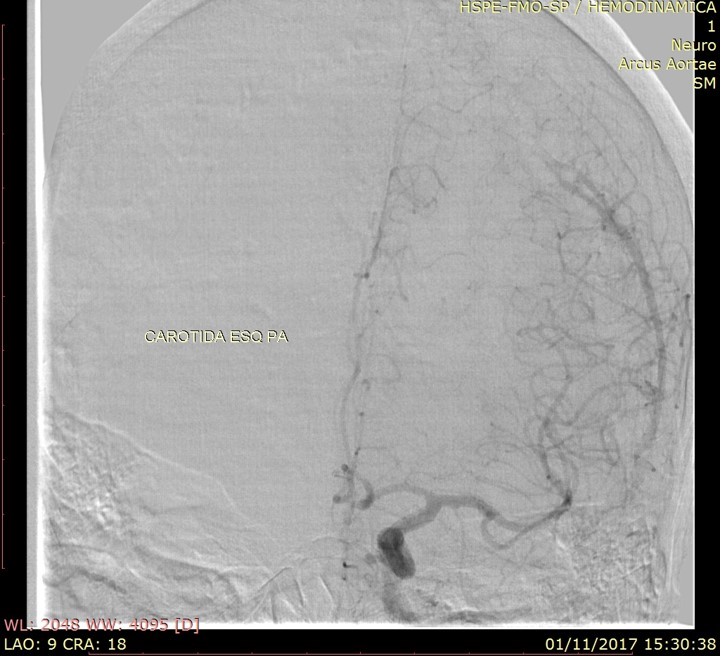

Discussão de tratamento de Fístula Arteriovenosa Dural grau I

Malformações artério venosas durais intracranianas - Discussão de caso fístula dural pós traumática grau I

Fístulas arteriovenosas durais (FAVDs) são lesões adquiridas, que consistem em uma ou mais conexões fistulosas no interior dos folhetos da dura-máter, envolvendo mais especificamente as paredes de um seio venoso dural ou as veias leptomeníngeas adjacentes.